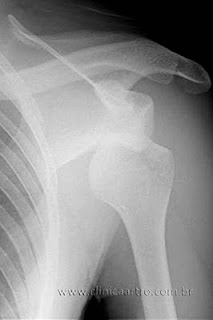

Quem pratica atividade física, principalmente de contato, como futebol ou artes marciais, quase sempre conhece alguma história de alguém que já “tirou o ombro do lugar”. Às vezes uma única vez. Às vezes, contam-se os episódios às dezenas. Mas parece que as pessoas estão mal informadas sobre esse problema, pois um trabalho publicado na Revista Brasileira de Ortopedia no mês passado mostrou que poucos sabem exatamente sobre a gravidade da lesão e menos ainda sobre como tratar. Apenas 22% dos pacientes citados pelo estudo receberam orientações adequadas sobre a doença e o seu tratamento. E nenhum – zero – recebeu orientações de por quanto tempo deveria ficar imobilizado. Antes, vamos dirimir uma dúvida: luxação é a perda do contato ósseo entre duas articulações. Ou seja, ocorre quando há um deslocamento e a “junta sai do lugar”. Pode acontecer com qualquer articulação e, ao contrário do que muita gente pensa, o termo luxação não deve ser utilizado para qualquer entorse, escoriação ou trauma de menor intensidade. Luxação é, assim como a fratura exposta, uma das urgências em ortopedia e deve ser tratada da forma mais rápida possível, para evitar complicações posteriores. Outro fato que deve ser considerado no tratamento é que quanto mais jovem for o paciente à época do primeiro episódio, maior a chance de recidiva.

Já em relação ao tratamento há pouca controvérsia. Entende-se que já a partir do segundo episódio o tratamento deve ser cirúrgico. A maior discussão se concentra nos casos de primeiro episódio. Alguns ortopedistas acham que o ideal é tratar cirurgicamente já no primeiro caso, pois a chance de recidiva é alta. Outros acham que sempre vale a pena dar “mais uma chance” ao ombro, e deixar o tratamento cirúrgico a partir de uma eventual segunda luxação.